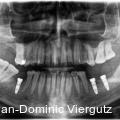

Der folgende Fallbericht beschreibt die funktionelle und ästhetische Rehabilitation eines 58-jährigen Patienten mit ausgeprägter Zahnarztangst, Kiefergelenkschmerzen und stark abrasivem Gebiss. Durch ein interdisziplinäres Behandlungskonzept mit 28 Multilayer-Zirkonkronen und implantatgestützter Versorgung konnte eine nachhaltige Verbesserung erzielt werden. Fotos: © ZTM Jan-Dominic Viergutz